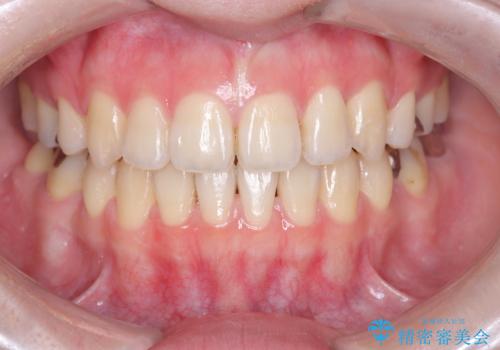

[ セラミック治療 ] 前歯の見た目を改善したい

![[ セラミック治療 ] 前歯の見た目を改善したいの症例 治療後](https://seimitsushinbi.jp/wp/wp-content/uploads/2025/10/IMG_9934-500x350.jpg?v=1761816431)